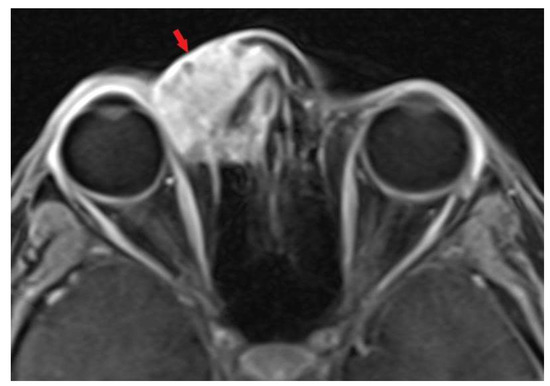

2. Case Presentation